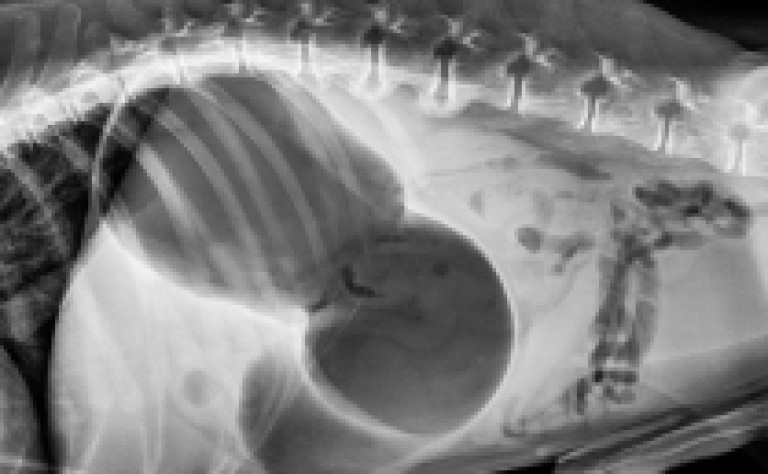

La torsion de l’estomac se produit lorsque l’estomac d’un chien se remplit de gaz, de fluide ou d'aliments et se tord sur lui-même.

Lors de la dilatation, l'estomac peut occuper plus de la moitié de la cavité abdominale !

Comme si votre chien avait avalé un gros ballon.

Finalement, le STDE est confirmé ou non grâce à une radio.